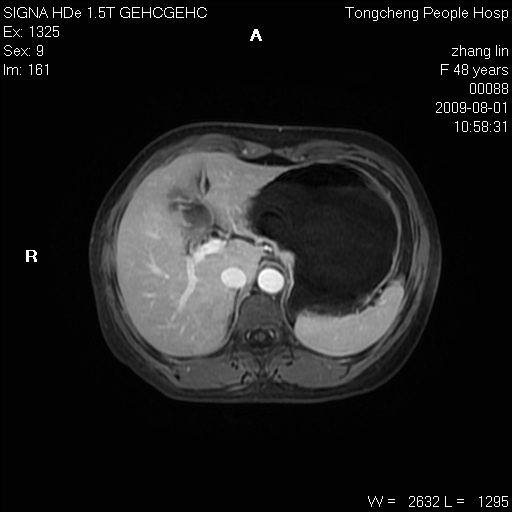

女,48岁。健康体检,彩超发现右肾占位性病变。平素健康。

临床诊断:右肾占位性病变,性质待定(囊肿?肿瘤?)。

上中腹部mr平扫+增强扫描,图像如下:

右肾上极见一类圆形病灶,t1wi呈等信号t2wi呈等高混杂信号,三期增强无强化,边界清---考虑囊肿出血。

同反相位均表现为等信号,病变无强化,考虑含蛋白的囊肿可能,弥散加权相或许有些帮助,